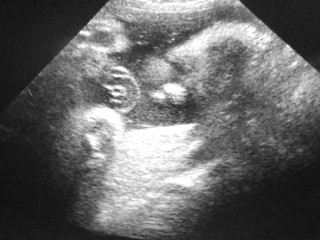

エコー写真での性別判断。 妊娠週数33週です。 お分かりになる方教えてくださいm(__)m お願いします。

やっとはっきり見せてくれたシンボル!!

男の子確定です♪

細めで小さ目だけどとっても元気な我が子です。

推定体重1,800gくらい